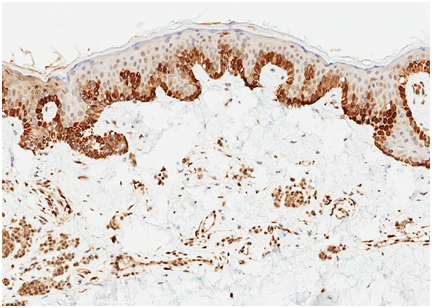

Following institutional review board-authorization, 13 primary cutaneous melanomas and 19 nevi were retrieved (5 common nevi, 5 mild dysplastic, 4 moderate dysplastic, and 5 severe dysplastic), (Figures 1-3). 5-μm formalin-fixed, paraffin-embedded sections were cut and mounted onto positively charged slides. Single IHC S100A9 staining was performed using the Leica Bond III protocol. All antibodies were purchased from Leica Biosystems (Buffalo Grove, IL). A board certified dermatopathologist evaluated S100A9 staining of melanocytes and keratinocytes in the epidermis of each sample. The pattern of staining was classified according to one of three categories: diffuse epidermal staining Figure 4, linear basement membrane staining Figure 5, and irregular patchy epidermal staining Figure 6.

Figure 1 H&E stain of malignant melanoma in situ of lesion A (hematoxylin and eosin, 40x).

Figure 4 Diffuse epidermal S100A9 stain of malignant melanoma in situ of lesion A.